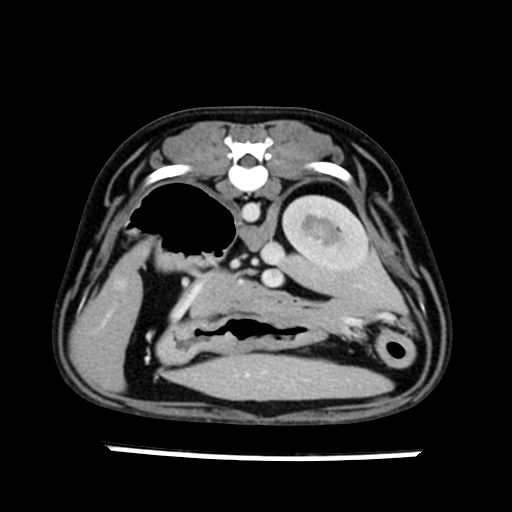

prescritto esame TAC

sequenza immagini limitata al fegato reni e surreni

le immagini ecografiche rispetto alla tac datano circa 7 mesi prima ,le surrenali sono normali nonostante il test acth sia risultato positivo .all’esame TAC dopo diversi mesi risultano aumentate armonicamente nel volume e si individua un forte sospetto di adenoma ipofisario .

sospetto adenoma ipofisario vs. meno probabilmente meningioma della base; intertiziopatia polmonare; lesione espansiva epatica, verosimilmente del lobo laterale sinistro, di sospetta natura neoplastica; lesioni spleniche di natura da definire; iperplasia/ipertrofia delle ghiandole surrenali, bilateralmente; vertebra di transizione del rachide toracico; tenosinovite cronica del muscolo bicipite brachiale di destra.